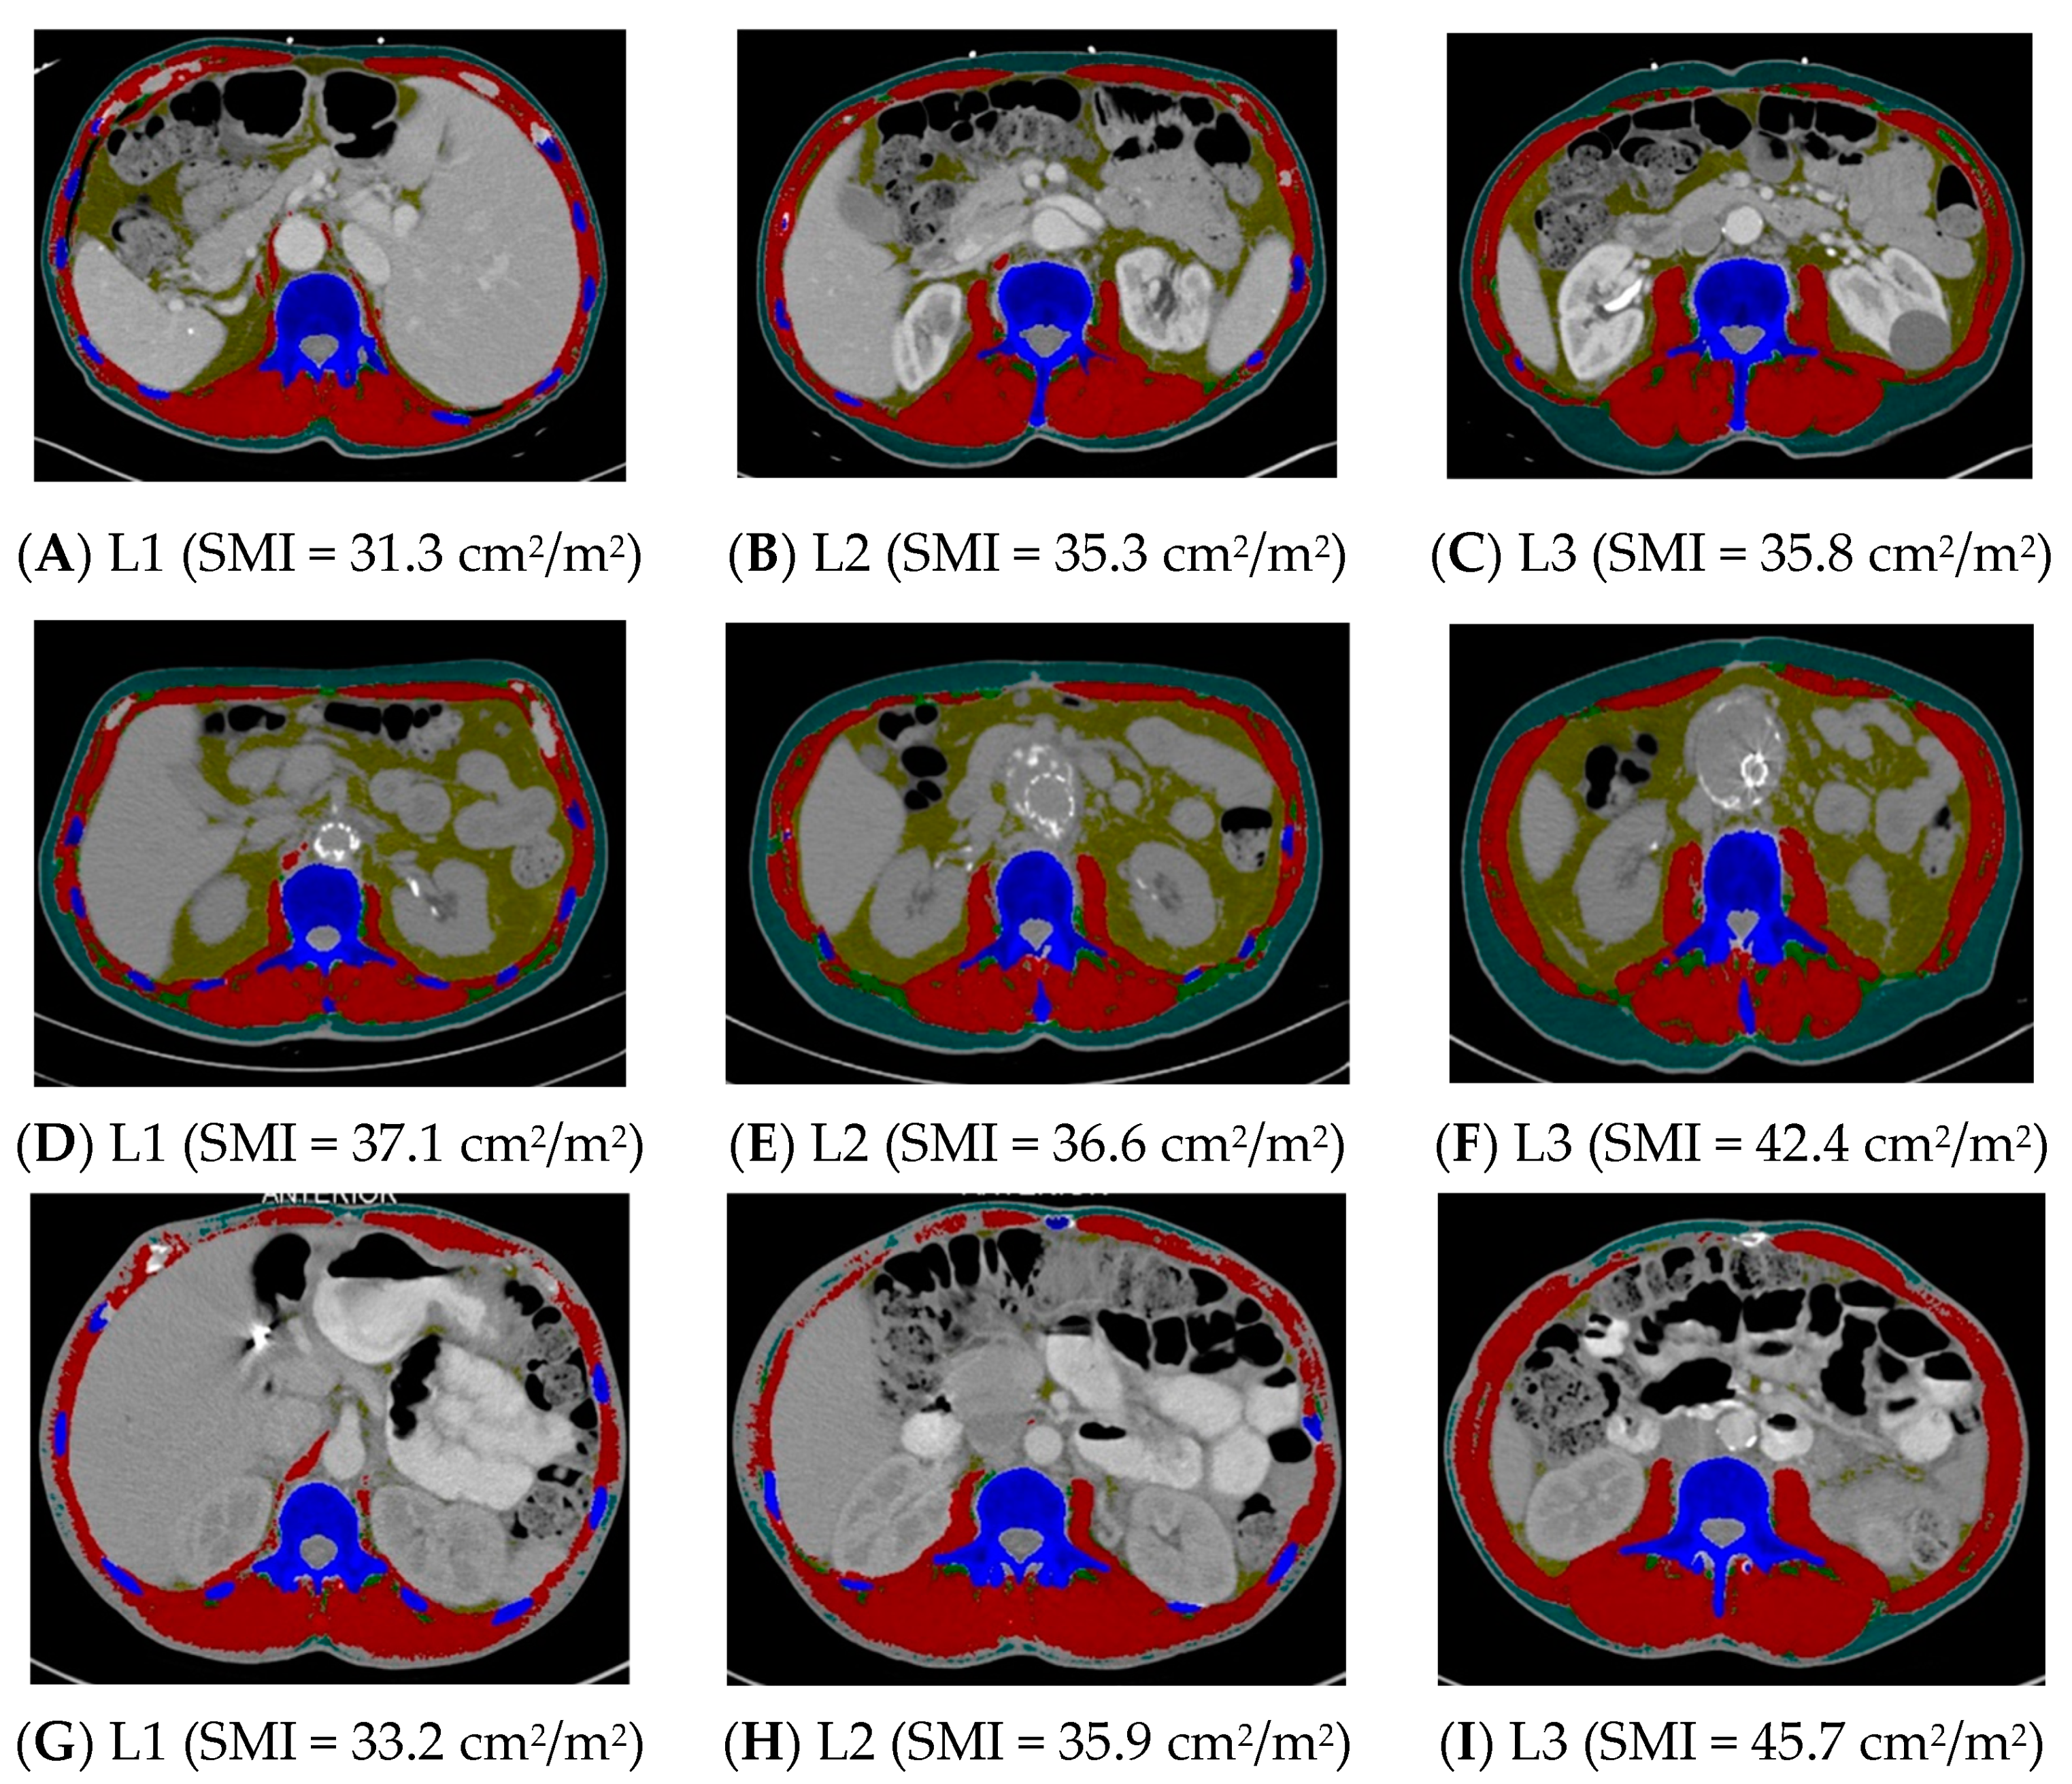

2.2. Assessing the Use of Alternative Vertebral Landmarks

5.3. Image Analysis

5.4. Primary Dependent Variables